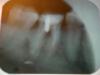

Ira G. Опубликовано 18 декабря, 2009 Поделиться Опубликовано 18 декабря, 2009 (изменено) Здравствуйте,. год назад мне наращивали часть зуба(левая шестерка), и установили штифт. Было это сделано как-то не очень удачно, очень долго болела десна, я полоскала рот(сода+йод), и через какое-то время на десне прорвался свищ. Гной вышел, все зажило и год я ходила спокойно. Две недели назад этот кусок зуба, который был нарощен, отвалился. Штифт остался на месте. Я пришла к стоматологу, мне все почистили, наростили заново и доктор сказал, что надо ставить коронку, так как от зуба осталась тонкая стеночка и долго он не продержится. Я согласилась ставить коронку. Мне обточили зуб, сделали примерку. И тут у меня снова воспалилась десна. Сегодня была на примерке коронки, и мне сделали рентген, и увидели, что как-то неправильно установлен штифт, от этого свищ. Рекомендовали курс антибиотиков проколоть в десну(сегодня сделали первый укол), и затем одевать коронку. Я переживаю. Я спросила, может быть лучше вообще удалить этот зуб и штифт, дать всему этому зажить, а затем уже придумать что дальше туда поставить? Но врач протезист сказал, что лучше все же оставить этот штифт, тем более, что он год меня не беспокоил. И возможно я несколько лет спокойно прохожу с этой коронкой(после того как антибиотики мы проколем). Что вы думаете, как лучше поступить в моем случае? И кстати, мне будут ставить не керамические коронки(которые я хотела), а цирконевые(?), объясняют это тем, что в моем случае меньше 50% зуба осталось, и он не выдержит керамику. Ну и видно особо не будет. Я расстроилась конечно, думала, в наше время уже не ставят металлические зубы. Прикрепила фото рентгеновского снимка. Лучше не получается сфотографировать, а сканера у меня нет. Буду очень благодарна за мнения. Изменено 18 декабря, 2009 пользователем Ira G. Ссылка на комментарий